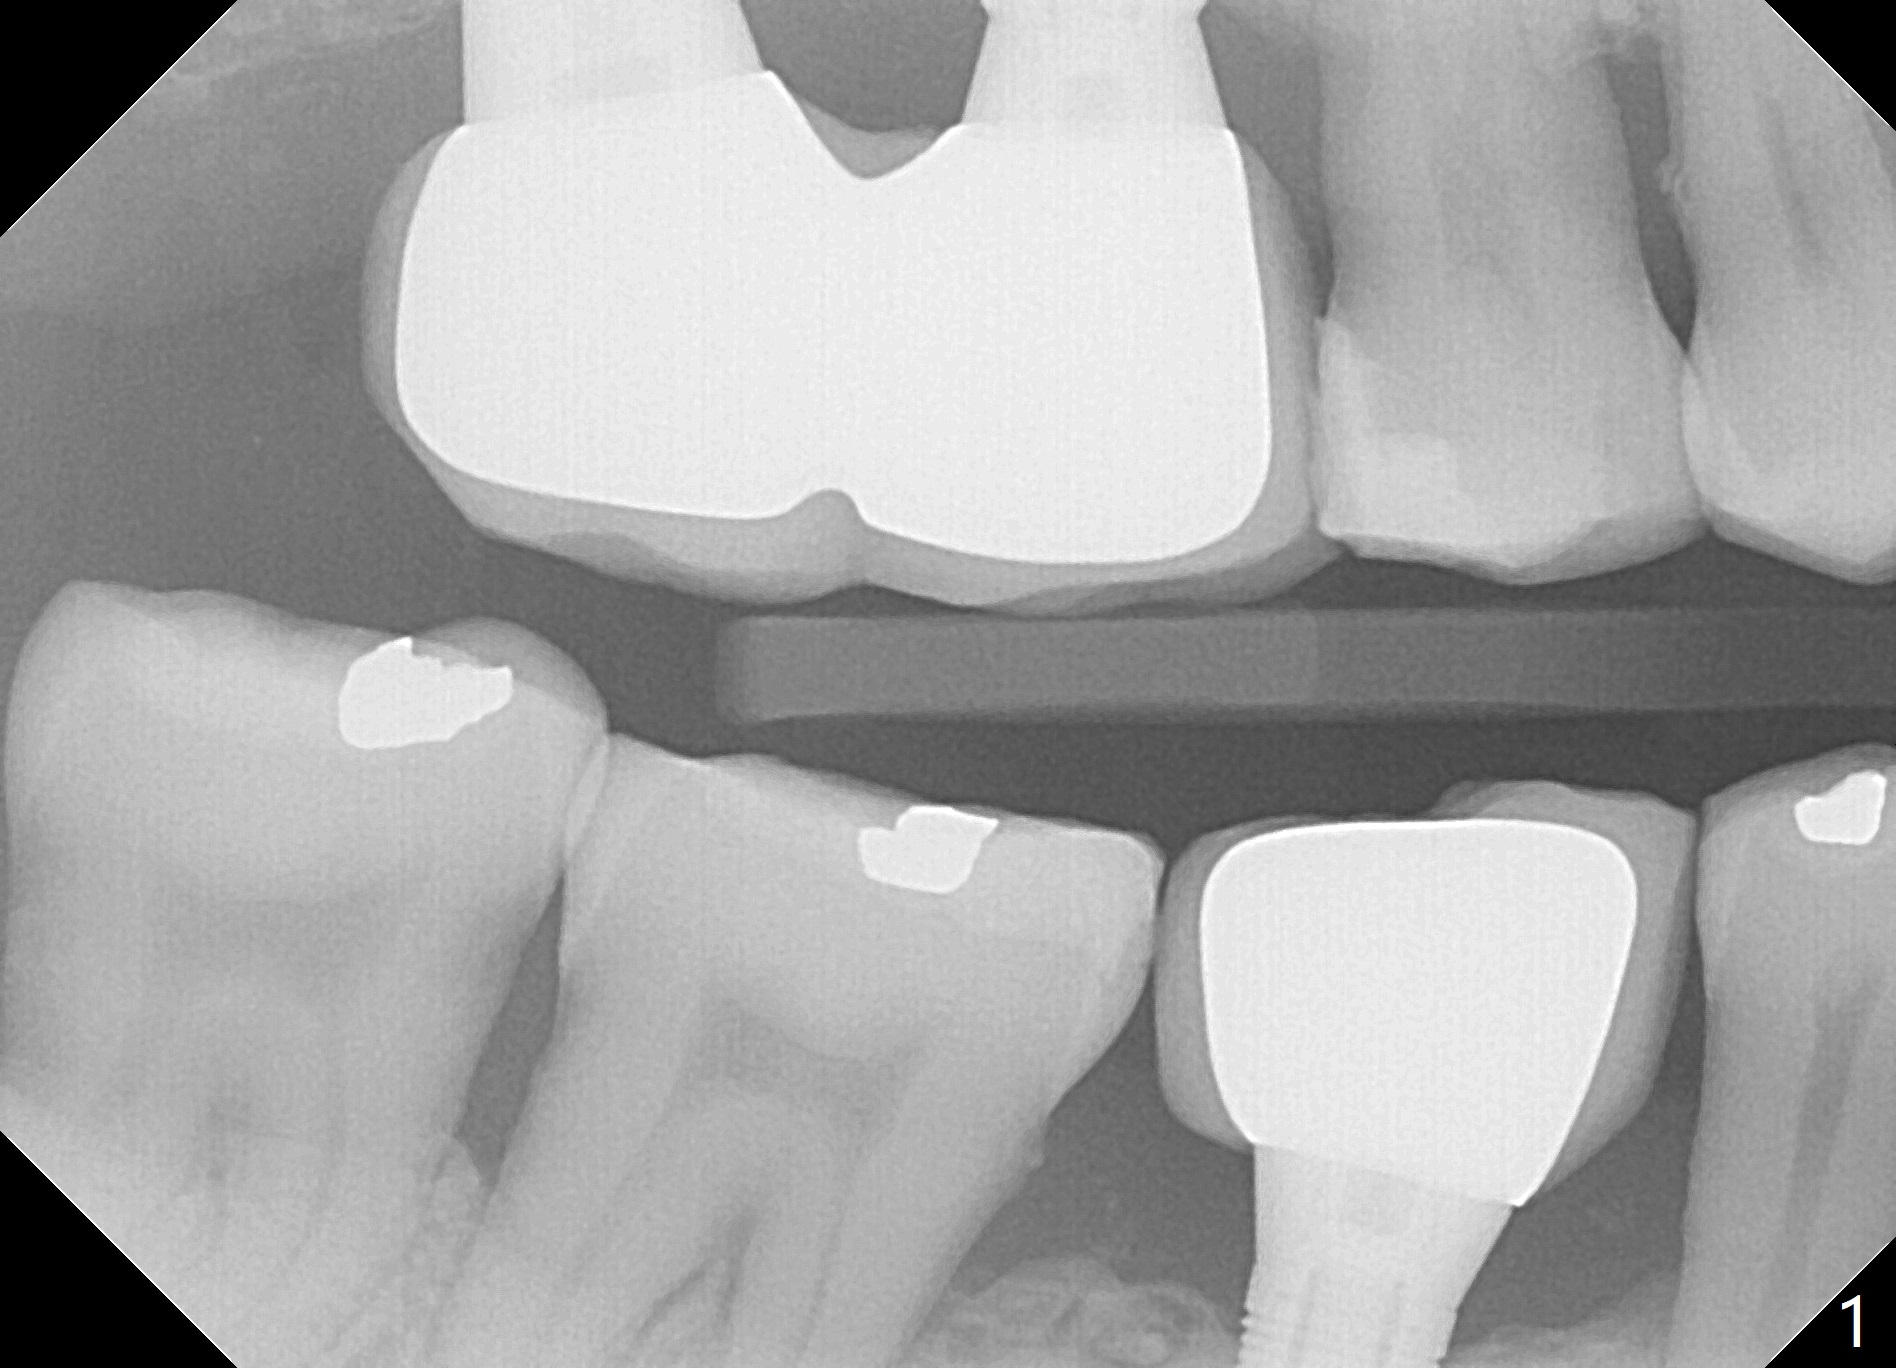

Improve Implant/Crown Ratio and Prevent Periimplantitis

A 59-year-old man seems to have perio-endo disease at #19 (Fig.1-3). To improve implant/crown ratio, place IS implant at the crestal level (not too deep). To prevent periimplantitis (buccal plate postop resorption), place the implant lingually. Prepare surgical handpiece to initiate osteotomy or to flatten the septum.